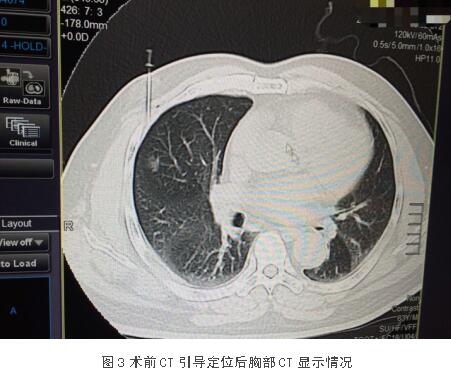

患者李某,男,63岁,发现肺部结节3月余。入住市中心医院后完善相关检查检验,并结合患者症状及体征,经检查患者无明显手术禁忌,符合手术指征,积极行术前准备,考虑结节较小且恶性程度可能性大。在杨斌主任医师与李卫国副主任医师的细致讨论下,交换意见后明确此类微小的肺结节于腔镜下较难寻找,加之CT片的解剖位置会发生一定变化(右肺不能膨起),难以利用触感去确定其具体位置及边界,尤其是质地与肺组织相近的占位,故决定术前1小时给予CT穿刺定位,明确占位方位及所需切割大致边界,以便后续手术安全且迅速实施。

对于较小肺部磨玻璃结节,往往给予肺楔形切除术或肺段切除术,特别是对于位于肺组织周围的“优势部位”的病灶。手术切除的基本原则是在保证病灶切干净的基础上,正常肺尽量少切除、多保留,这样术后的肺功能、生活质量会更高。由于结节小、密度低,单孔微创下手指很难触及到结节从而准确定位,这样有可能导致切缘肿瘤残留、或切除过多的正常肺组织以及增加手术时间。因此术前定位可以帮助手术医生在手术过程中顺利确定病灶位置,从而精准地切除病灶,保留足够的切缘以及更多的正常肺组织,患者获益最大。